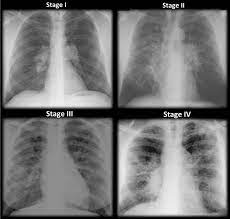

Pancreatic cancer may be diagnosed as diabetes, due to the fact that diabetes is often a symptom or risk factor of pancreatic cancer. One report notes a case of systemic sarcoidosis that mimicked the symptoms and metastatic spread of cancer. Since sarcoidosis and lung cancer can be present concurrently, performing biopsy to obtain pathology results from any suspected lung lesion in a patient diagnosed with sarcoidosis is essential. When referring to the stages of sarcoidosis, this is referring exclusively to pulmonary sarcoidosis. Sarcoidosis is known to be a cancer mimicking and masking condition, it can follow cancer or develop concurrently with cancer, and significantly increased risk of cancer can affect sufferers of sarcoidosis. Although it is most commonly thought to be a lung disease, sarcoidosis has been shown to affect almost any organ. There are currently no formal recommendations to guide the differential diagnosis workup between the evolution of lymphoma or a solid cancer and a granulomatous reaction associated with neoplasia. Apparently, lymphomas can sometimes harbor sarcoidal granulomas within cancer — and this change, although rare, is thought to perhaps reflect an immune reaction to the cancer tumor, and not the systemic disease, sarcoidosis.

Pancreatic cancer may also be misdiagnosed as gallstones or pancreatitis, or the inflammation of the pancreas. After some conversations and research i now know sarcoidosis can be mistaken for cancer. A condition called sarcoidosis, most commonly found in the lungs, can be mistaken for cancer, tuberculosis, or other infections, as its symptoms are similar. I've been going to support groups for the disease for 20 years now and find 3 or 4 patients a year who are diagnosed initially as having lung cancer. That same fungal infection is often frequently mistaken for squamous cell carcinoma, or skin cancer, when it shows up on the skin. Sarcoidosis can also affect calcium metabolism, the nervous system, the liver and spleen, muscles, bones and joints, the kidneys, lymph nodes, or any other organ. Various organs can be affected including the skin, lymph nodes, and liver. Sarcoidosis and neoplasia, especially lymphoma, can show overlapping presentations, thus making the diagnosis and treatment harder to deal with. Copd is a term used for a group of obstructive lung diseases. There are currently no formal recommendations to guide the differential diagnosis workup between the evolution of lymphoma or a solid cancer and a granulomatous reaction associated with neoplasia. Since sarcoidosis and lung cancer can be present concurrently, performing biopsy to obtain pathology results from any suspected lung lesion in a patient diagnosed with sarcoidosis is essential. Despite careful preparation, it thus remains difficult to distinguish between these conditions even when lymph nodes are strictly evaluated. Only 10 similar cases had been reported previously.